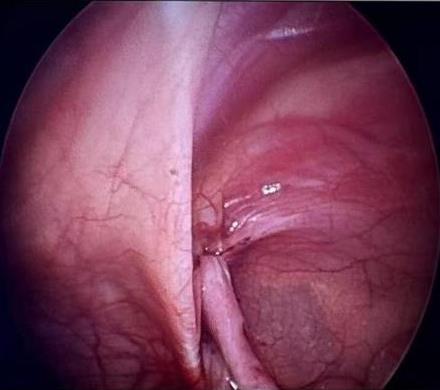

• 膈下静脉在后腹腔镜下左肾上腺切除术中的应用

2025, 31(11):75-82. DOI: 10.12235/E20250184

摘要 (51) HTML (18) PDF 1.95 M (50) 评论 (0) 收藏

摘要:目的 探讨以左膈下静脉为解剖标志,优先解剖肾上腺中央静脉,在后腹腔镜左肾上腺切除术(RLLA)中的可行性。方法 回顾性分析2021年1月-2023年12月于该院行RLLA的116例患者的临床资料,根据手术方式的不同,将患者分为实验组(以左膈下静脉为解剖标志,并优先解剖肾上腺中央静脉的RLLA)和对照组[传统“三层面法”解剖性后腹腔镜肾上腺切除术(RLA)],各58例。比较两组患者术中及术后24 h临床指标、应激指标、免疫功能和并发症。结果 两组患者顺利完成RLLA,且无1例中转开放手术。实验组手术时间、找到中央静脉时间、引流管留置时间和术后住院时间明显短于对照组,术中出血量和术后引流量明显少于对照组,差异均有统计学意义(P < 0.05);两组患者术后胃肠功能恢复时间比较,差异无统计学意义(P > 0.05)。两组患者术前炎症因子、应激指标和免疫功能指标比较,差异均无统计学意义(P > 0.05);两组患者术后24 h的白细胞(WBC)、C反应蛋白(CRP)和白细胞介素-6(IL-6)明显高于术前,且实验组明显低于对照组,差异均有统计学意义(P < 0.05)。两组患者术后24 h的丙二醛(MDA)明显高于术前,超氧化物歧化酶(SOD)和谷胱甘肽过氧化物酶(GSH-Px)明显低于术前,且实验组MDA明显低于对照组,SOD和GSH-Px明显高于对照组(P < 0.05)。实验组术后24 h的CD4+和CD4+/CD8+明显低于术前,且实验组术后24 h的CD3+、CD4+和CD4+/CD8+明显高于对照组,差异均有统计学意义(P < 0.05);两组患者术后24 h的CD8+比较,差异无统计学意义(P > 0.05)。实验组发生术中血压波动率明显低于对照组,差异有统计学意义(P < 0.05);两组患者均未发生腹膜损伤、肾蒂血管损伤和腹膜后血肿。结论 RLLA中以左膈下静脉作为解剖标志,优先解剖肾上腺中央静脉是可行的,可以改善手术指标,减轻应激反应和免疫应答,具有临床推广应用价值。